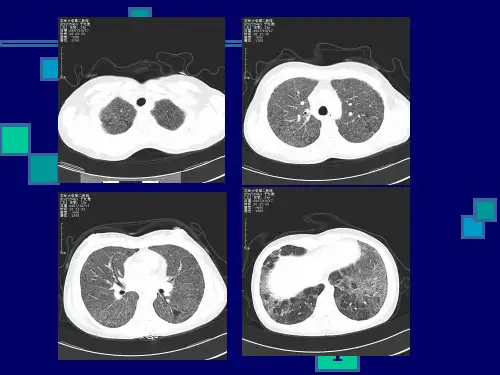

肺挫伤